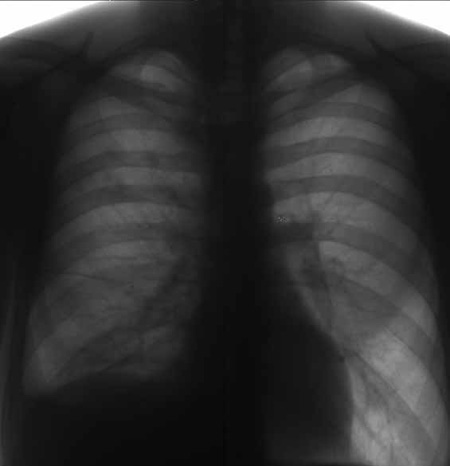

Может стать первым проявлением туберкулеза легких, Микобактерия туберкулеза может поразить отделы легких, расположенные наиболее поверхностно, рядом с плеврой (оболочка, покрывающая плевру), в таких случаях сначала проявляются признаки плеврита, так как микобактерия поражает и плевру. Развивается воспаление с постепенным разрушением плевры рядом с очагом в легких.